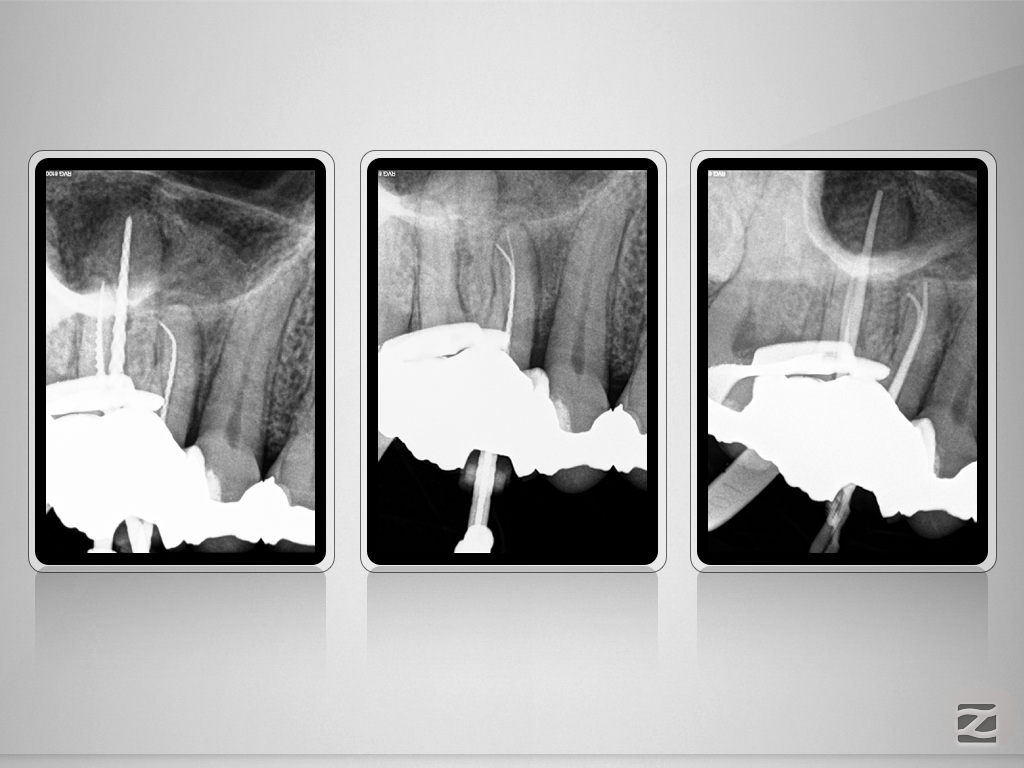

Immer schön skeptisch bleiben 4